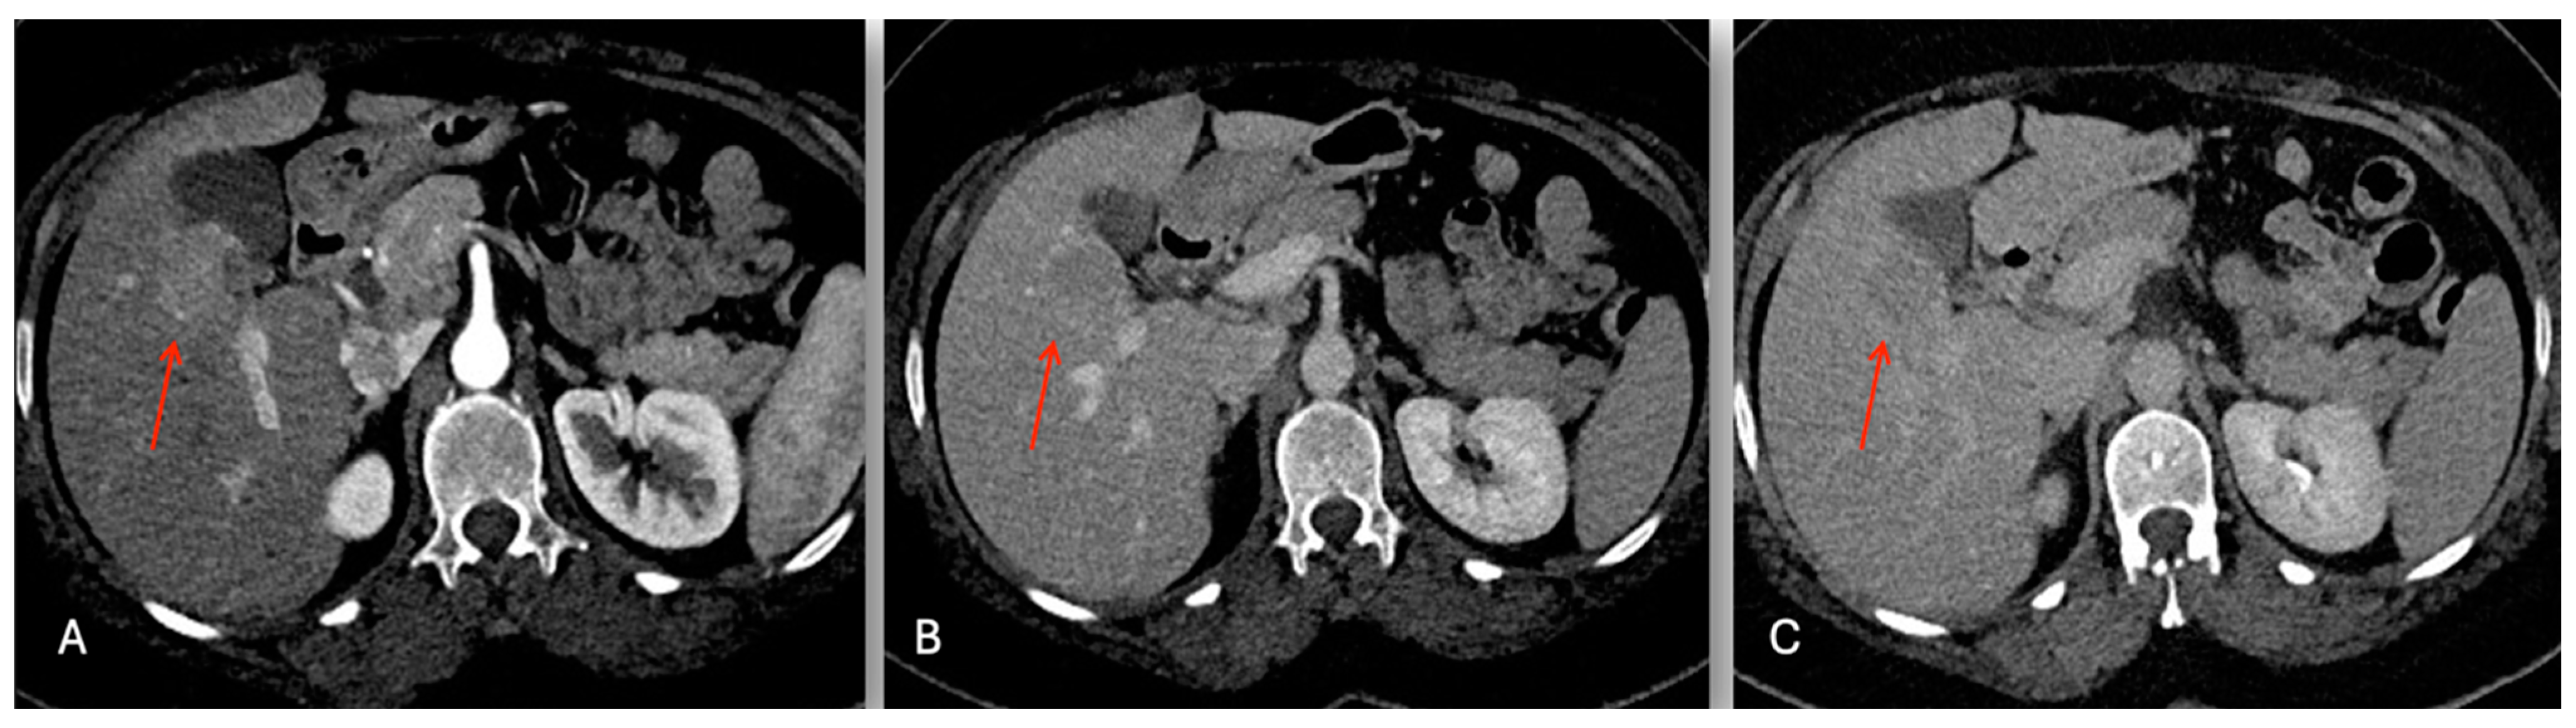

3.2.1. Case 1

3.2.2. Case 2